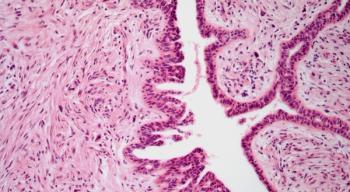

A 71-year-old woman with a past medical history of rectal cancer presents with complaints of her “eyes not working.” Physical exam is notable for incongruent bitemporal visual field defects. An MRI of the brain with gadolinium contrast was obtained. What is the diagnosis?